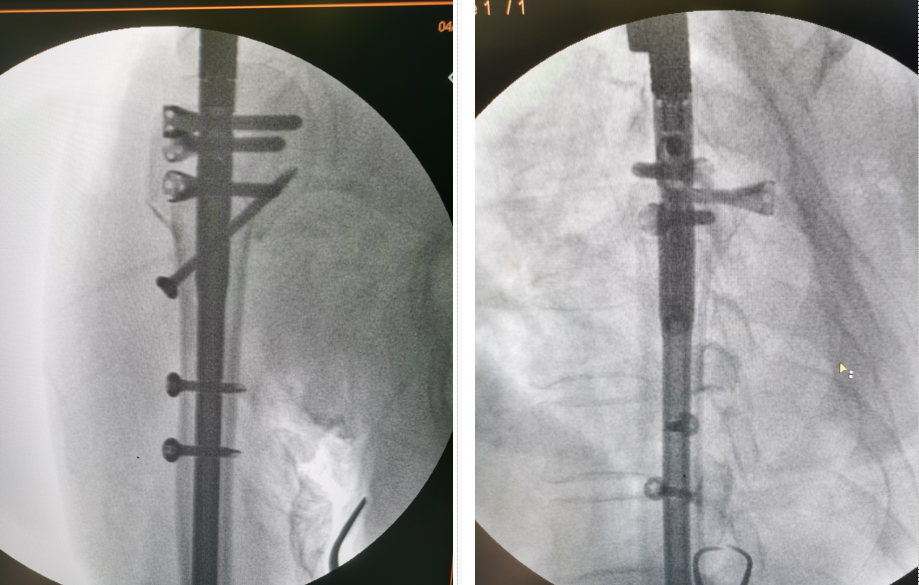

近日,我院骨創外科一病區成功為一名肱骨近端四部分骨折患者實施小切口復位肱骨多維髓內釘(Multiloc)內固定手術,取得滿意療效。該手術在我院尚屬首例,填補了棗莊地區、魯南地區在該領域的空白,在山東省內亦屬于領先水平,標志著我院創傷骨科在此領域的微創手術進入了一個更高的水平!

患者,女,73歲,因騎車時摔倒,左上肢著地導致左肱骨近端粉碎性骨折,收住我院骨創外科一病區。楊猛副主任接診后,給予患者詳細的查體,并完善術前檢查。左肩關節三維CT示患者為較為復雜的肱骨近端粉碎性骨折,骨折塊移位較大,分型為四部分骨折。出現該類骨折的患者往往骨質疏松較為嚴重,骨質量差,骨折粉碎較重,傳統切開復位接骨板固定為偏心性固定,容易出現內固定松動,導致手術失敗,且切口大、剝離多、出血多。為讓患者以最小的創傷代價獲得最大程度的肩關節功能,經團隊術前討論,決定為患者實施目前在國內最先進的肱骨近端粉碎性骨折小切口復位肱骨多維髓內釘(Multiloc)內固定手術。

在制定了周密的手術計劃和康復計劃后,由楊猛副主任主刀,朱法豪主治醫師擔任助手,在麻醉科張顯平副主任醫師、手術室張建永護士長的共同配合下,應用手術室先進的X光全透視手術床,成功完成了手術。

該微創手術與傳統術式相比,手術時間短,出血少,創傷小,固定方式為多維平面鎖釘中心性固定,更為牢固,患者能夠早期進行肩關節功能鍛煉,因此能取得更為滿意的治療效果。